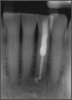

If a tooth stands alone, greater forces will be placed on it because it has no adjacent teeth to provide support. This situation will affect the decision-making process for placing a post. Figure 3 shows a tooth that was on an island and would be having three implants placed in front of it. The tooth would take a much greater beating than another tooth that had support proximally. Even though it had a good root canal, the clinician would need to account for whether the tooth would last until the implants integrated. Figure 4 shows a case that would quickly proceed to implants. The patient had a less-than-ideal bridge for over a decade, with decent endodontics and functionality. There was also an overhang on the premolar. The post was not ideal in this case because there was one distal canal and not all the gutta-percha was removed from it. An intimate fit should be the goal with the post and the walls. Whether using a threaded or non-threaded post, there should not be excess gutta-percha because it is not as solid as the tooth and will lead to greater movement. That movement on the tooth and bridge will create too much force and result in demise.

Fig 4. Case that quickly would proceed to implants.

Figure 4